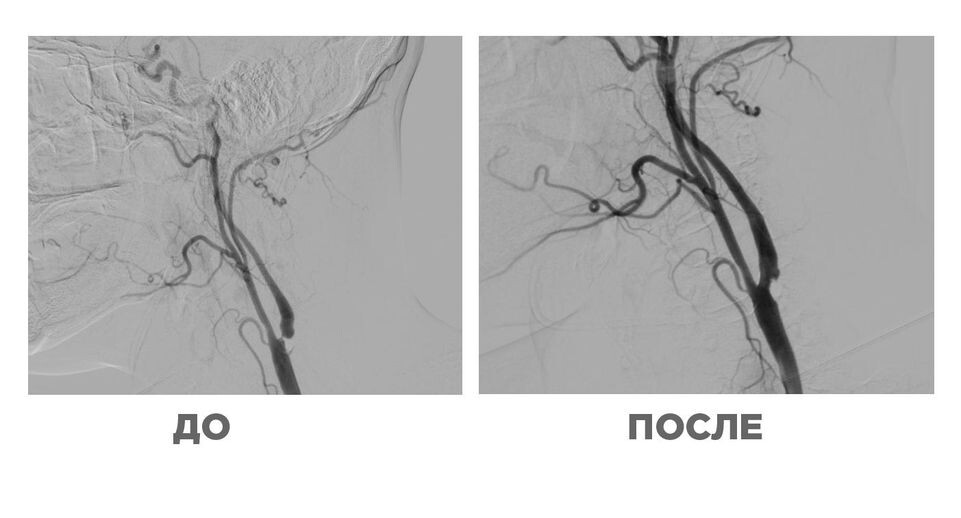

Врачи из больницы Сергиева Посада спасли мужчину с повторным инсультом и 95% закупоркой артерии. Мужчина 45 лет потерял связность речи и двигательную функцию конечностей с правой стороны.

Сосудистый хирург Игорь Дядьков рассказал, что чаще всего инсульт в таком молодом возрасте — это наследственность. У пациента причиной стала бляшка, которая перекрывала почти 90% кровотока в левой сонной артерии.

«В ходе исследования подтвердился стеноз, то есть сужение сонной артерии на 95%. Причем структура бляшки была по структуре и твердости сравнима с человеческим зубом», — уточнил врач.

Мужчине провели операцию, и он уже уверенно держит ложку и восстанавливает речь.